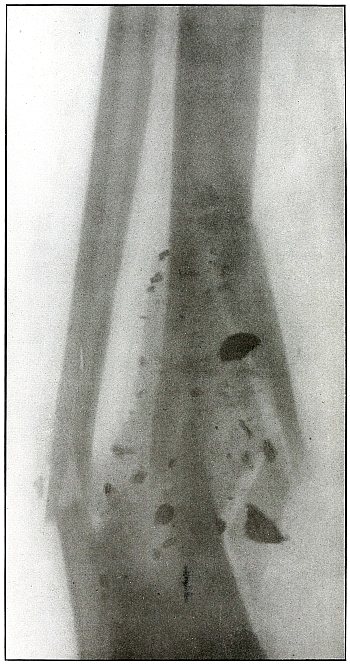

The treatment is conservative.

Results should be favorable. Infection would depend most probably upon the asepsis of the first dressing. [Pg 150]

Plate 70.

_

[Pg 151]

Rifle—Plate 70.

LOWER EXTREMITY.

Gunshot Fracture of the Tibia,

with Lodgment of the Missile.

The course of the bullet was from within outward, striking the posterior surface of the tibia about 2 inches above the ankle, and causing a slight crack in the bone at the point where its course was deflected.

The velocity was that of extreme range, as the wholly normal outline of the projectile and the slight penetration indicates that its energy was almost entirely lost in flight and not by ricochet.

The sharp outlines of the lower border of the fibula and the external border of the articular surface of the lower end of the tibia indicate the position of the fibula as next to the photographic plate.